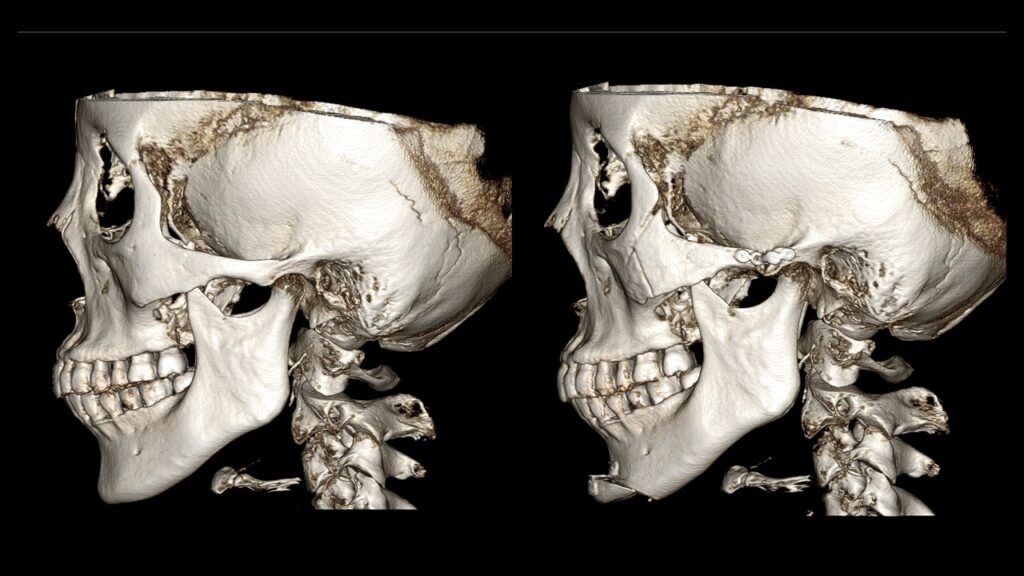

4. Case Studies (3DCT & Medical Photos)

Case 2: (Zygoma + Chin Advancement + Face Lift + Brow Lift) Dramatic improvement in the side profile and double chin within just 1 month.